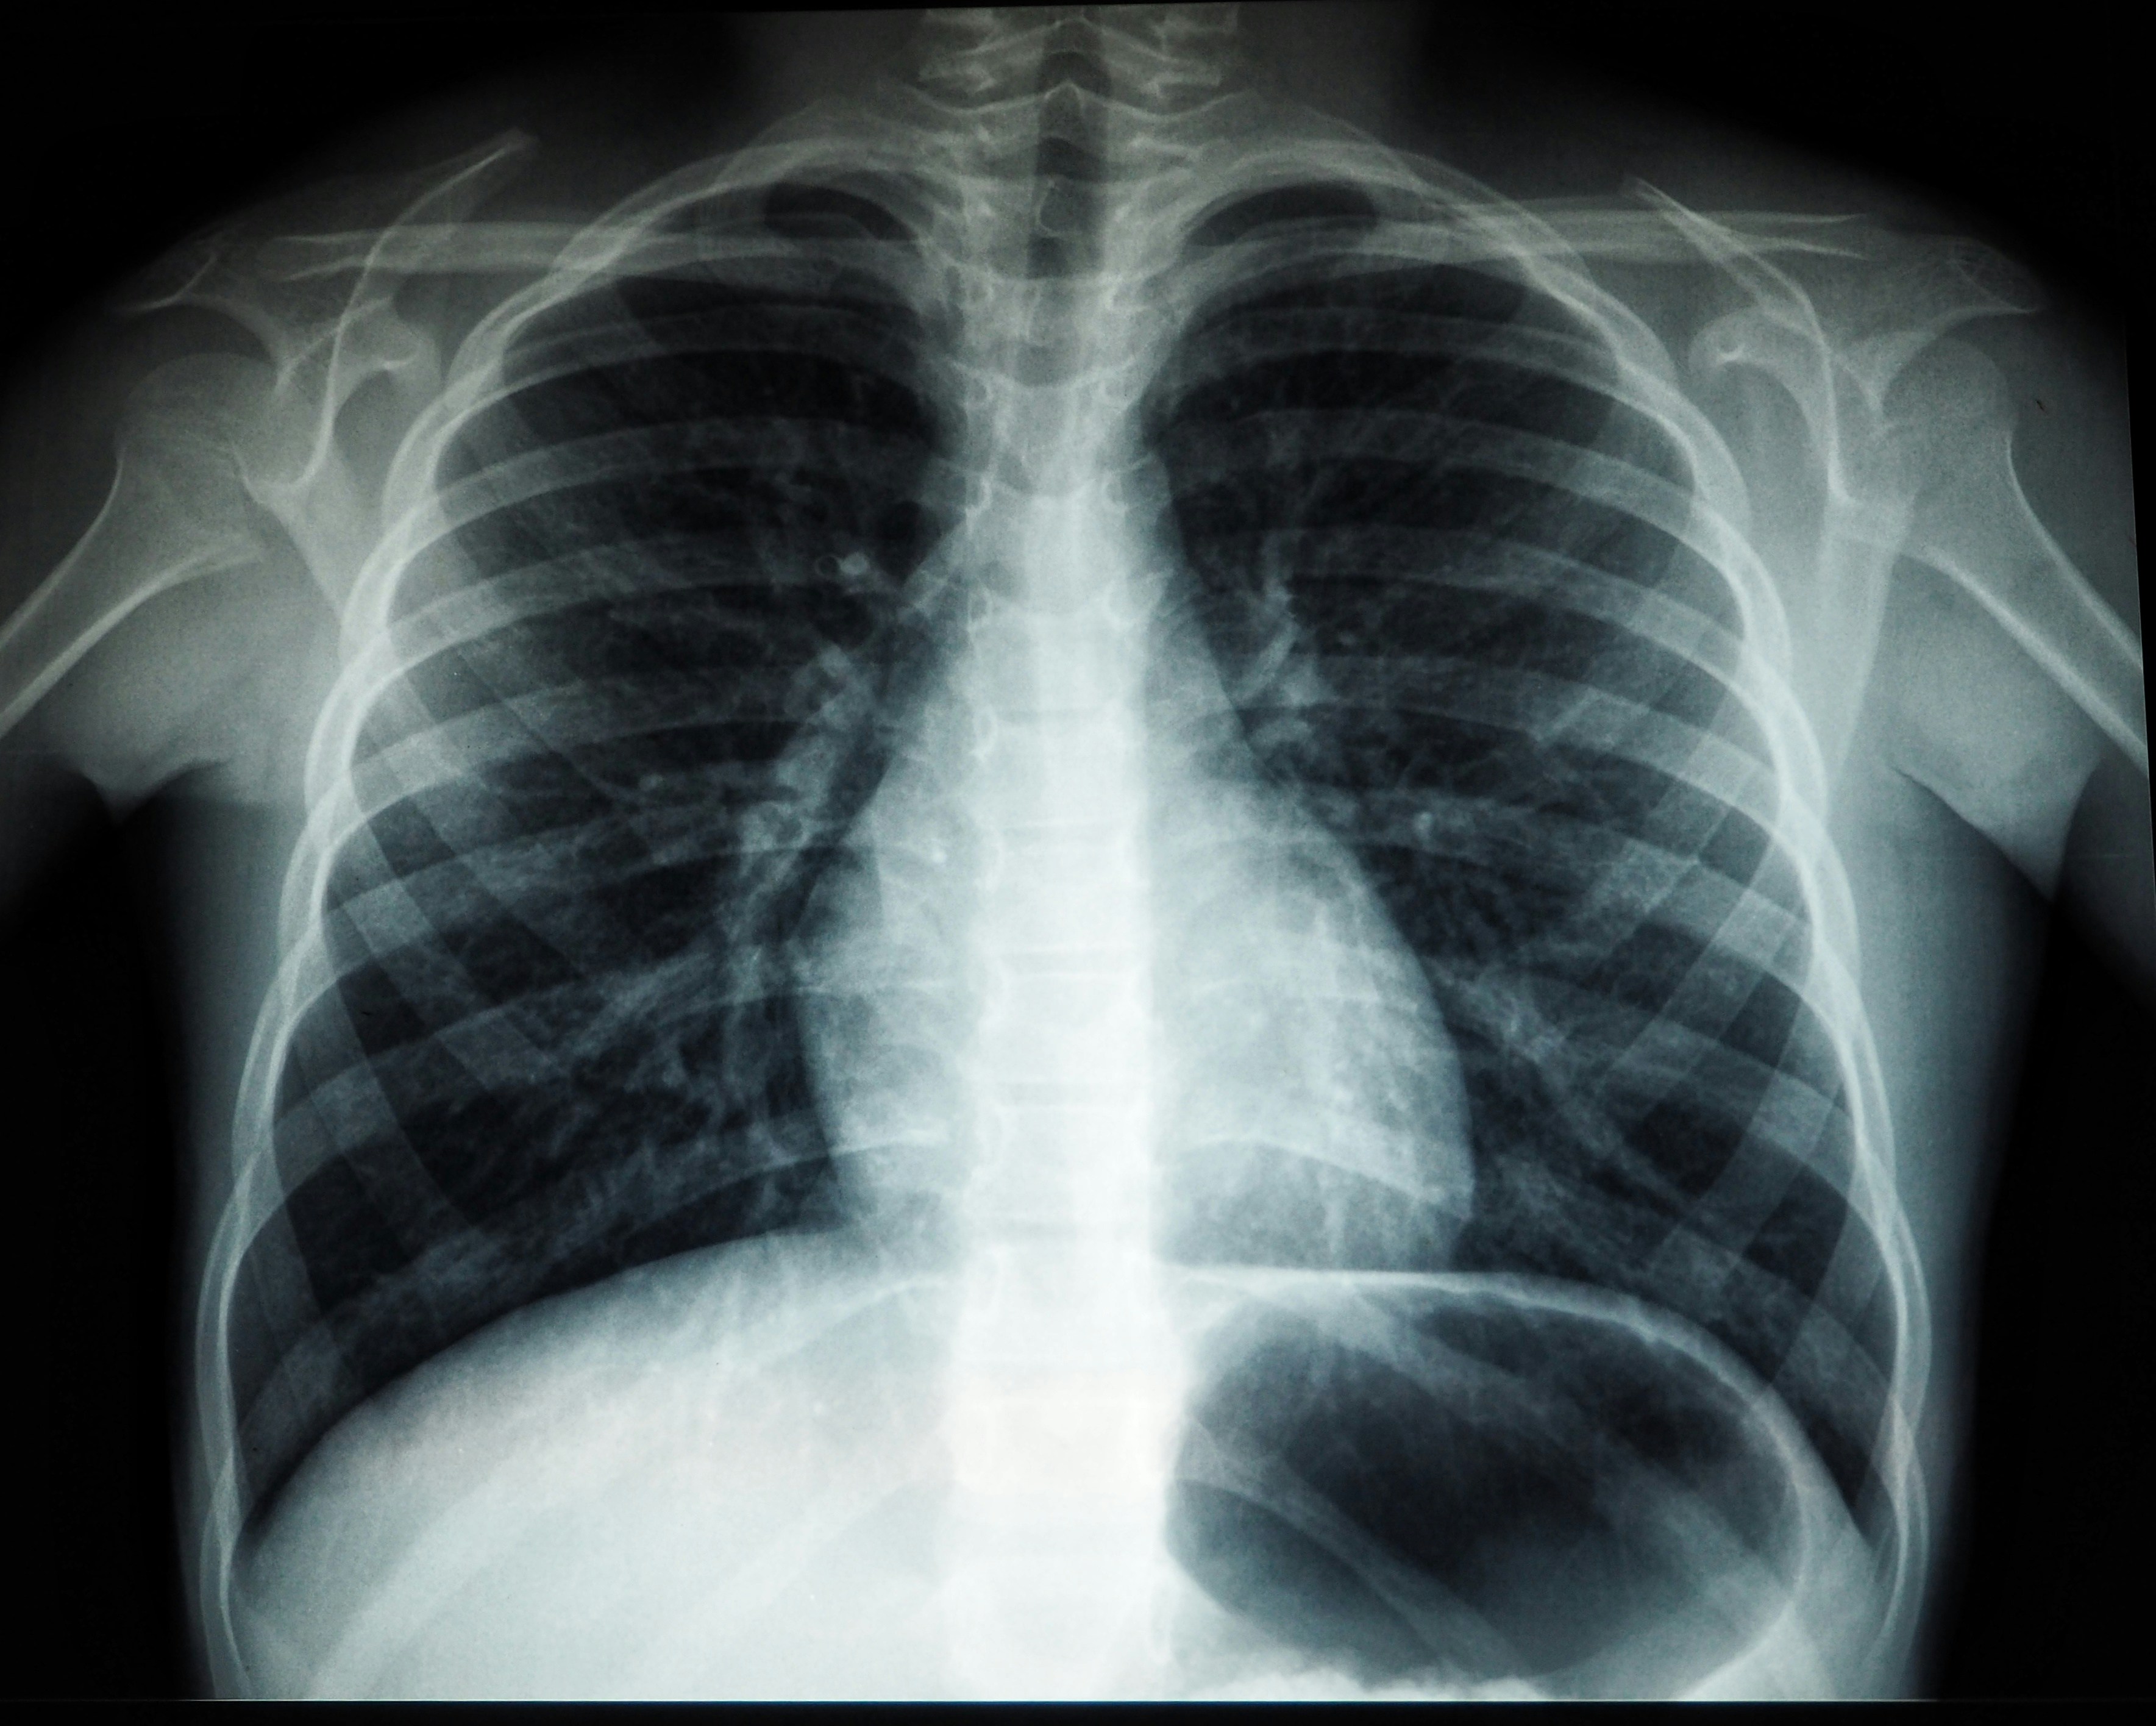

TB caused 2.5% of deaths in India between 2021-2023. (Image: Unsplash)